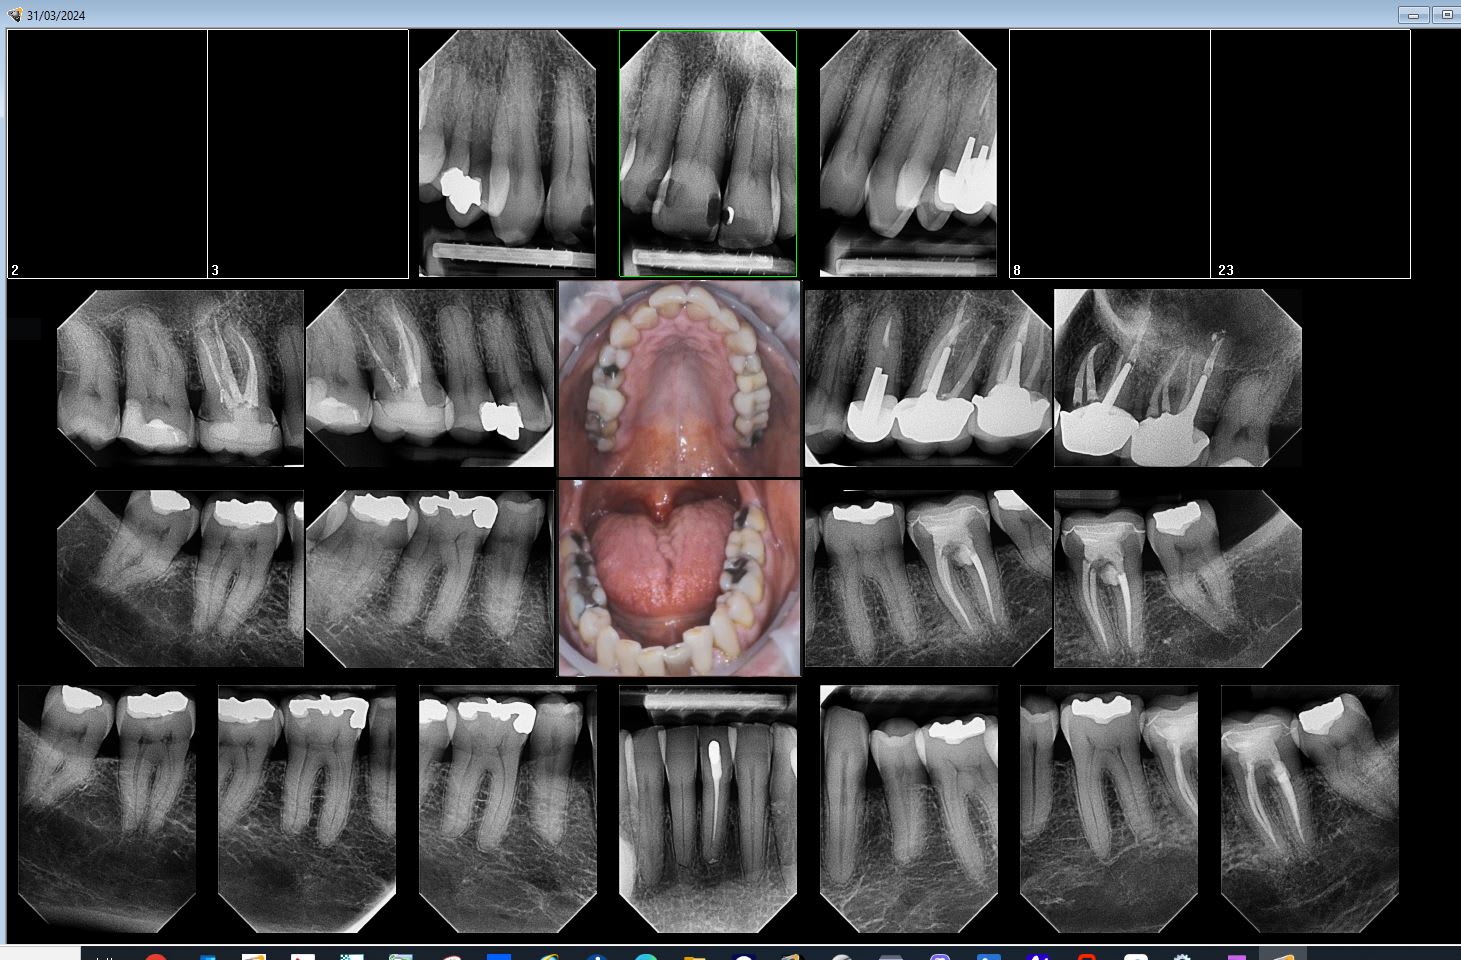

Tiens status meilleur rapport qualité - prix capteur taille 2 isensor woodpecker 1500 balles camera MD960 150 balles. Qui dit mieux ?

Q7hzhmdtbcm7o90tyozq57rg5b05 - Eugenol

CS 6200 VS I sensor wood pecker

--

U1hmcyehazycn2ogu4ihlnk89fs9 - Eugenol

01/04/2024 à 05h55

Tu peux faire ça aussi.

Ztazqvfo0icuajk94i1s5e4ijsx6 - Eugenol

Cherchez l'erreur.

W5hwweso1i5f9e2gccviwihkyxxi - Eugenol

Capteur.

Capture d  cran 2015 03 12 12.28 - Eugenol

Plaque . -)